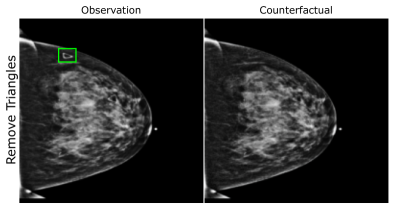

EMBED

Using prior insights, we apply our mechanisms to a real-world artefact removal task on the EMory BrEast imaging Dataset (EMBED) (Jeong et al., 2022). Schueppert et al. (2024) observe that triangular and circular skin markers are spuriously associated with breast cancer in classifiers due to shortcut learning (Geirhos et al., 2020), and manually labelled 22,012 affected mammograms. Using this dataset, we train a significantly scaled-up, amortised, anti-causally guided semantic mechanism () to remove skin markers. We model triangular markers (), circular markers (), breast density (), and cancer () as independent parents of the mammogram , and remove artefacts by intervening on and while holding and fixed. Figure 6 shows that our mechanisms effectively remove artefacts and can disentangle representations for triangles and circles. We successfully remove of triangles and of circles in our test set - a noteworthy result given the dataset’s small size and the scarcity of labelled skin markers (Appendix I).